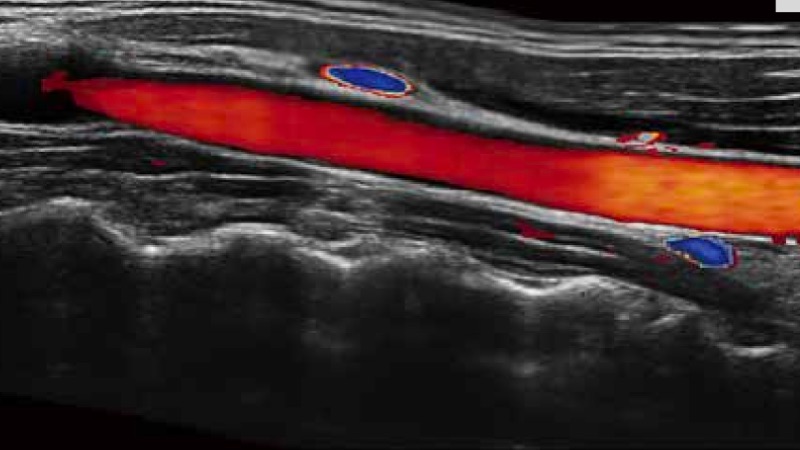

開立醫(yī)療通過不斷的技術(shù)創(chuàng)新,為大眾的生命健康提供持續(xù)關(guān)愛。P12 Plus采用全新一代超聲成像平臺(tái),新平臺(tái)旨在將真實(shí)還原組織解剖結(jié)構(gòu)作為首要目標(biāo)。平臺(tái)采用全新集成化硬件模塊,搭載新一代芯片,系統(tǒng)性能得到大幅提升,為您的診斷提供了豐富的臨床信息。優(yōu)異的圖像表現(xiàn),豐富的探頭配置,全面的應(yīng)用功能,為您日常診斷提供了可靠的助手。

彩色多普勒超聲診斷系統(tǒng)